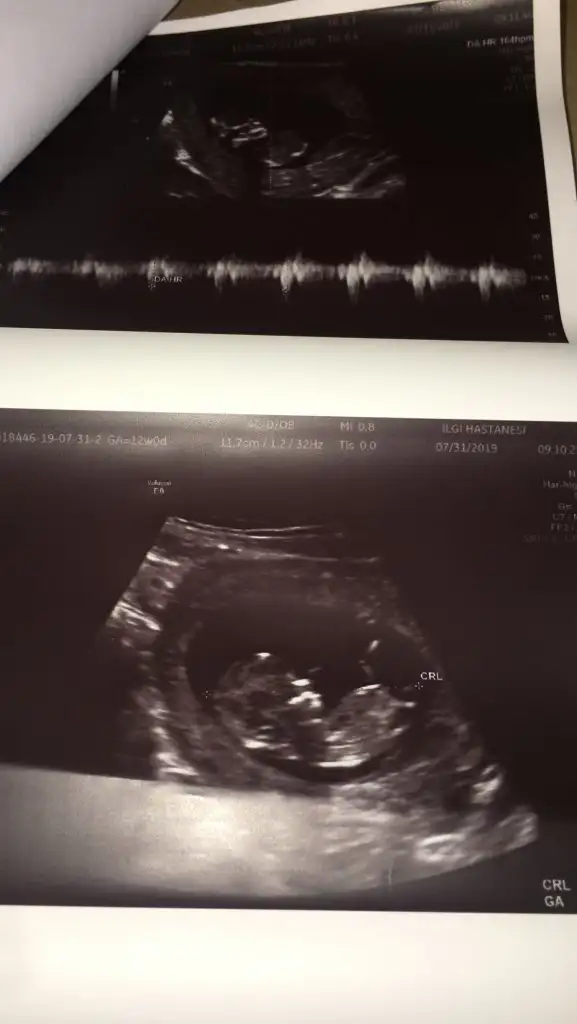

Erkek benceyaa lütfen bana da bi tahminde bulunsanız.Bi oğlum var bide kızım olsun çok istiyorum ama sağlıkla gelsin inşallah tabi en önemlisi o.Çokta merak ediyorum 11+4 şuan

Kız gibi geldi bana doktorunuzun tahmini neydi acaba?Eki Görüntüle 2301484 Eki Görüntüle 2301484 Eki Görüntüle 2301484 kızlar sizce cinsiyeti ne 9 haftaligim daha

Canım doktorum birşey demedi 9 haftalığa yeni girdim 3 hafta sonra kontrolüm var ozaman söylücek galibaKız gibi geldi bana doktorunuzun tahmini neydi acaba?

Altı yada yedi haftalık görüntünü de atarmışın canmEki Görüntüle 2301494 Eki Görüntüle 2301495 Merhaba bende tahmin alabilirmiyim

Valla çoo anladığımdan değil de başın konumuna göre tahmin yapıyorlar genelde sizin baş solda erkek mi ki acaabaMerhaba bizi de yorumlarsanız seviniriZ

Biz de bilmiyoruz daha gitmedik ilk bebek heycanlıyım o yüzden tahmininizi merak ettimValla çoo anladığımdan değil de başın konumuna göre tahmin yapıyorlar genelde sizin baş solda erkek mi ki acaaba